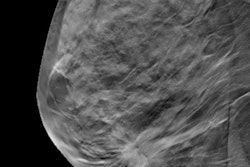

Current flat panel x-ray detectors used in mammography exams, for instance, are rigid and uncomfortable for patients. In the past few years, advances have been made in developing flexible sensing devices that can be readily shaped to fit in "nonplanar" scenarios. However, even in this advanced field, active sensing materials for x-ray panels are made with heavy metals, such as lead and cadmium.